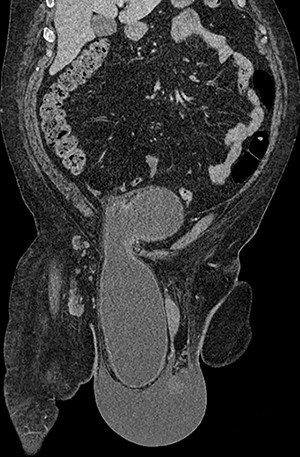

Computed tomography (CT) scan of the abdomen and pelvis with contrast revealed a large right indirect inguinal hernia containing a significant portion of the bladder within the scrotum (Figs 1–3). There was associated bilateral hydronephrosis and hydroureter, and significant scrotal oedema seen within the soft tissues.

Coronal CT image of the abdomen and pelvis demonstrating herniation of the bladder through the inguinal canal into the scrotum, with associated oedema of the scrotal soft tissues.